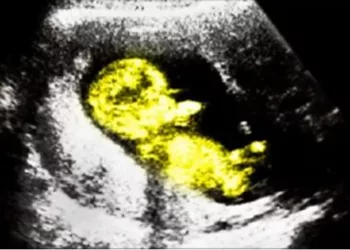

Nașterea acestui bebeluș poate fi considerată un caz extrem de rar. Kate Mason, o tânără însărcinată din America, în vârstă...

Sarcina este, de obicei, o experiență magică pentru mame, dar ultimele două săptămâni pot avea multe provocări. Este foarte important...